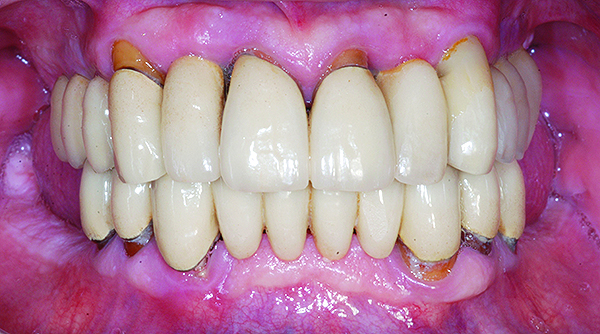

The maxillary prototype was adjusted, polished, and left to function with the mandibular provisional. The definitive maxillary zirconia restoration was then completed from the information provided by the prototype, and the cutbacks for the facial porcelain (Nos. 6 through 11) were done after milling but before sintering. Subsequently, the mandibular prototype was adjusted to the sintered and colored maxillary zirconia framework before the application of porcelain to Nos. 6 through 11 and final glazing (Figure 11). Following this step, the mandibular definitive monolithic zirconia restoration was milled, colored, and sintered. The facial porcelain (Nos. 6 through 11) was applied, and then both maxillary and mandibular restorations were stained and glazed (Figure 12). Both bridges were inserted at the same time (Figure 13 through Figure 15). Minor occlusal adjustments and oral hygiene access was verified and the zirconia surfaces polished. The bridge screws were torqued to 20 Ncm according to the manufacturer’s recommendation, and No. 24 was luted with a provisional cement. Postoperative radiographs were taken (Figure 16).

Fig 15. Intraoral frontal view of completed maxillary and mandibular zirconia restorations.

Figure 15